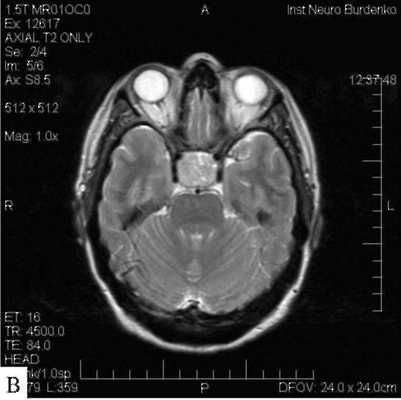

МРТ гипофиза с контрастом и без: А- гипофиз нормальных размеров (обведено кругом), В - симметричные кальцификации (стрелки)

Вопрос что лучше сделать: “МРТ гипофиза с контрастом или без?” - должен решить врач. Последний порекомендует приемлемые для получения качественных изображений характеристики аппарата: сканы, сделанные с помощью низкопольных аппаратах с открытым контуром малоинформативны. Оптимально пройти обследование на томографе с мощностью от 1,5 Тесла.

Учитывая размер гипофиза (с горошину), МРТ преимущественно выполняют с введением контрастного вещества. В качестве красителя используют растворимые соли (хелаты) гадолиния, которые не представляют опасности для организма и при накоплении тканями обеспечивают лучшую визуализацию. Побочные эффекты встречаются менее, чем у 1% людей. Контрастирование ограничивают:

МРТ гипофиза с контрастом в детском возрасте до 12 лет проводят в стенах больницы. Усиленную магнитно-резонансную томографию назначают в рамках предоперационной оценки перед удалением опухоли (в том числе аденомы) или кисты мозгового придатка, для определения характера изменений тканей после вмешательства (позволяет дифференцировать сформировавшийся рубец от рецидива новообразования) и пр. В качестве дополнительного способа проводят еще и КТ, которая лучше демонстрирует изменения, исходящие из костных структур и показывает патологии турецкого седла, кровоизлияния в питуитарную железу. МРТ гипофиза без контраста малоинформативна.